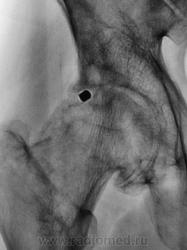

Почему-то на ум пришло сразу "Вот пуля пролетела ,и ага..".

это вероятно и есть состояние после огнестрельного ранения в виде ДОА 3 ст, инородное тело или нет?

Для точной локализации пули нужна попендикулярная ( как в "Двух капитанах" - палочки должны быть попендикулярны) проэкция. Может и не причина артроза?